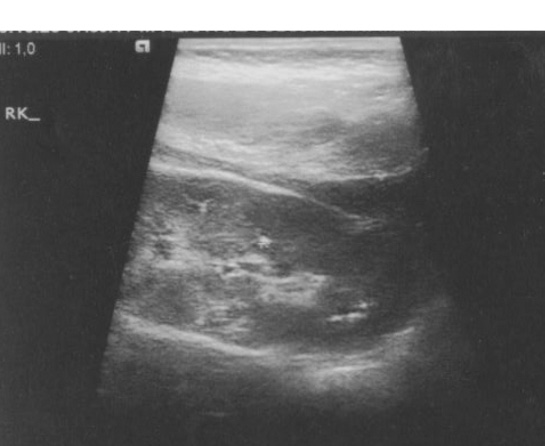

A 1-year old male patient presented because stones were found on US which was performed following urinary tract infection at the age of six months. In his history, it was learned that the mother and two daughters of the mother from the previous marriage had renal stones and the uncle was lost because of chronic renal failure 14 years ago. System findings were found to be normal on physical examination. Multiple calcifications with the larges one being 2 cm were found in both kidneys on repeated urinary tract US (see figure).